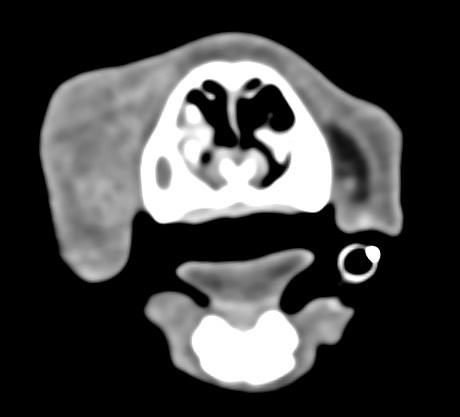

狗狗電腦斷層掃描 不明原因口腔出血 嚴重牙周病 口腔惡性腫瘤 鱗狀上皮細胞癌(Squamous cell carcinoma,SCC)

主訴嘴巴突然流血 口腔潰爛 左下顎腫脹 同時有嚴重牙周病 經由口腔採樣 電腦斷層掃描 確認為鱗狀上皮細胞癌(Squamous cell carcinoma,SCC)同時已經侵犯下顎骨。確診後經由外科醫師、腫瘤科醫師、電腦斷層影像科醫師共同擬定治療計畫後

,大範圍切除左下顎,經過一年追蹤,目前狗狗一切安好喔。

*電腦斷層影像

貓咪 下顎骨骨折

頭骨結構較為複雜 頭骨骨折相對於四肢長骨骨折 不容易靠xray 完整評估術前需要靠電腦斷層影像檢查評估骨折狀況才能良好評估手術方式 提高成功率